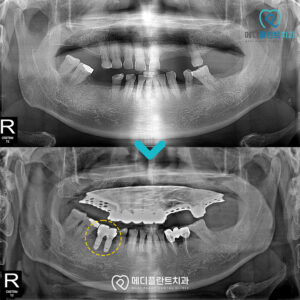

춘천수면치과 어르신분들도 편안하게! 유치가 탈락하고 맹출하는 영구치는 말 그대로 영구적으로 평생 사용해야 하는 치아입니다. 한 번 상실되면 더 이상 새로 자라지 않기 때문에 오랫동안 건강한 상태로 유지하기…